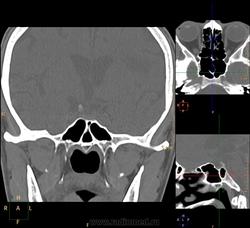

Вроде основных две, но разнообразные перегородки делят их на бОльшее количество:

Тут, например, 7 камер у одной пациентки: